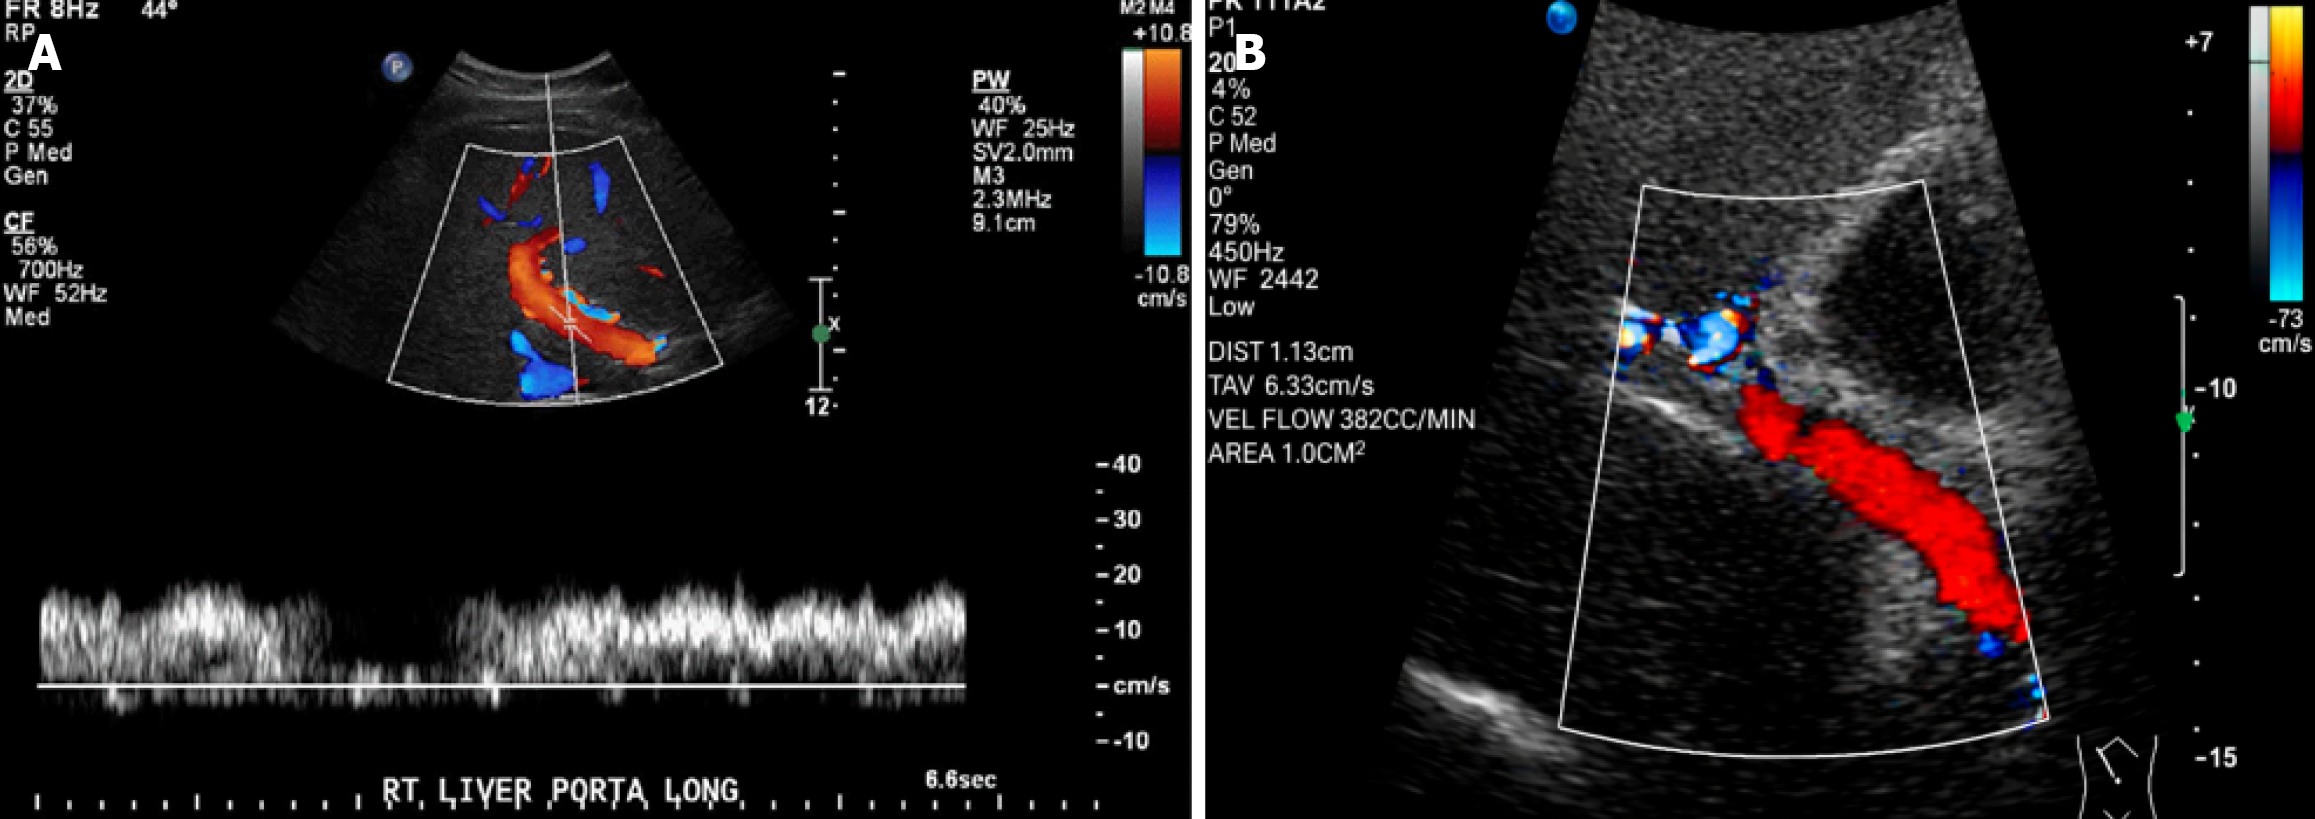

Abdominal ultrasound and doppler: All subjects underwent examination with a 3.5 MHz transducer (Philips iU22). Liver size, spleen bipolar diameter, and PVD were measured. Liver enlargement was defined as > 2 cm below the right costal margin without deep inspiration. Cirrhotic morphology was identified by a coarse nodular echo pattern, shrunken size, and predominant caudate lobe[14]. PVD was measured where it crosses the inferior vena cava during quiet respiration; > 13 mm indicated portal hypertension[15]. Splenomegaly was defined as a bipolar diameter > 130 mm at the left midaxillary line[16]. Hilar varices and prominent splenic veins (> 10 mm) were noted. The abdomen and pelvis were scanned for ascites. Portal venous flow parameters (peak systolic velocity, flow volume) were assessed via Doppler ultrasound.

Doppler ultrasonography revealed significant hemodynamic changes in cirrhotic patients. The PVD and flow velocity in a healthy control are illustrated in Figure 2. In contrast, portal hypertension in a cirrhotic patient, characterized by an increased PVD and reduced flow velocity, is demonstrated in Figure 3.

Radiologically, we observed a stepwise increase in both spleen size and PVD, progressing from healthy controls to compensated cirrhosis and culminating in the most significant enlargement in patients with variceal bleeding. This progressive splenomegaly and portal venous dilation provide direct anatomical evidence of escalating portal hypertension, confirming that these ultrasound parameters effectively mirror the hemodynamic burden of advancing liver disease (Table 4). The Doppler ultrasound findings are visually demonstrated in Figures 2 and 3, where the PV’s progressive dilation and portal flow velocity reduction indicate the hemodynamic alterations associated with portal hypertension (Figures 2 and 3).